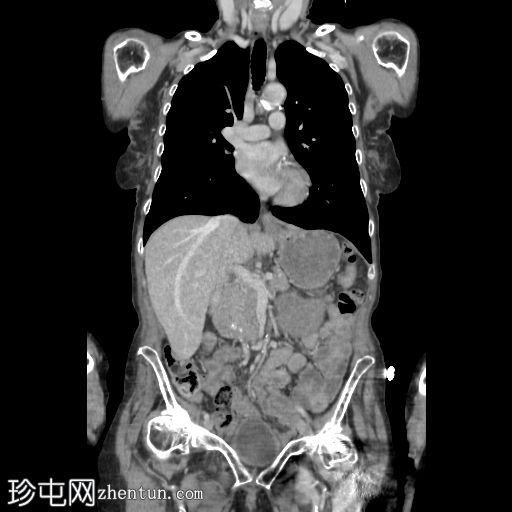

冠状位增强扫描(门静脉期)

5.jpg

三个月后,患者因急性腹痛伴呕吐就诊。

影像表现为小肠梗阻,移行区位于右侧闭孔疝处。疝囊内有少量积液,提示缺血性改变。

无气腹。